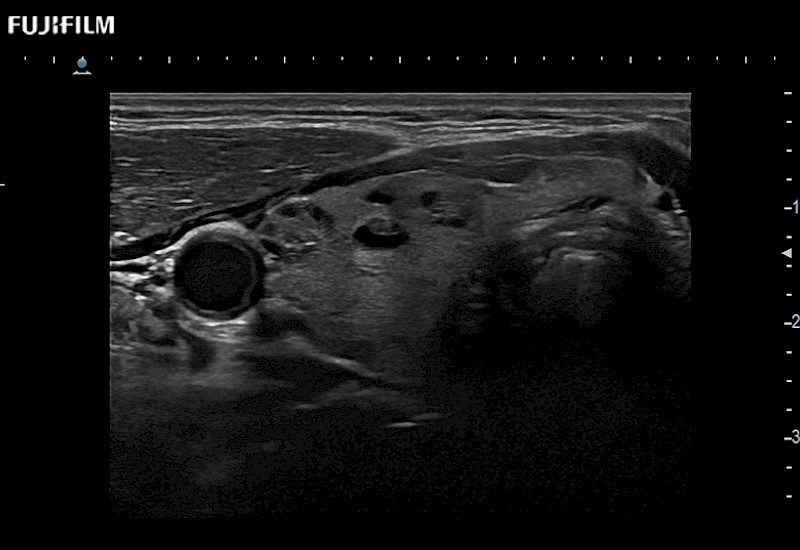

Fujifilm Healthcare understands that Surgical Oncologists demand excellence in their operating rooms — from their staff and the equipment they depend on. Fujifilm Healthcare's dedication to Surgical Oncologists provides outstanding ultrasound technology, professional support and the specialized tools necessary to best perform comprehensive real-time ultrasound imaging.

For precise surgical oncology ultrasound imaging, Fujifilm Healthcare offers premium level solutions that include:

for use during open and laparoscopic procedures: Tumor localization & staging, Ablation, Resection, Biopsy, Transplant, Abdominal exploration, Robotic surgery

Our dedication to Surgical Oncology allows us to offer superior image quality, outstanding system reliability and intuitive use of cutting edge technology.